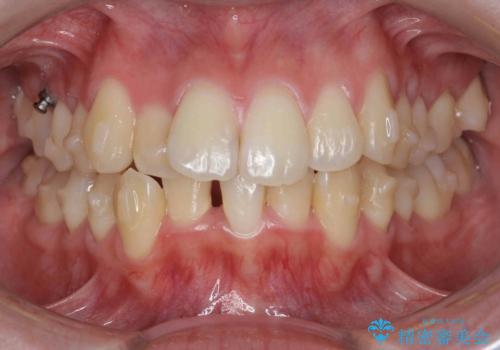

前歯のがたつきをマウスピース矯正できれいに!

- 目立つ前歯のがたつきを改善したい、と矯正治療を希望され来院されました。

今回の治療ではシミュレーションでしっかりと検討した結果、下顎は前歯を1本抜去し仕上げる治療計画としました。